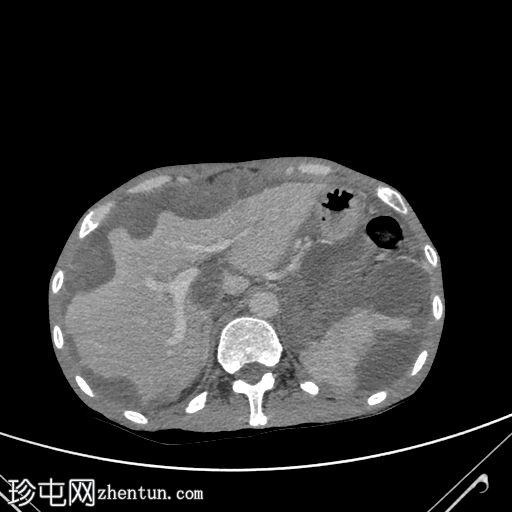

轴位增强扫描(门静脉期)

大网膜和肠系膜内可见低密度、不均匀的腹膜积液,脏器表面呈扇形凹陷,尤其以肝脏和脾脏最为明显。

阑尾肿大,长 5.0 cm,直径 1.2 cm,大小符合,可能提示阑尾黏液性肿瘤